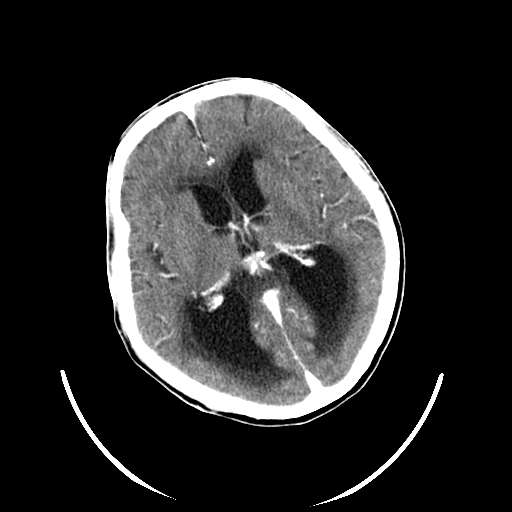

以下是引用zhangzhongshou在2007-10-8 19:16:00的发言:[br]大脑大静脉瘤[br]

以下是引用hhcckk在2007-10-9 10:03:00的发言:[br]galen';s静脉瘤又称大脑大静脉瘤,是由于动静脉短路,大量血流进入galen';s静脉(大脑大静脉),造成该静脉瘤样扩张所致,病理上典型的galen';s静脉瘤包括一明显扩张的囊状galen';s静脉和引流galen';s静脉的短路血管,,这些短路血管多来源于颈内动脉系统或基底动脉系统,多异常扩大、迂曲。巨大的galen';s静脉瘤可造成中脑压迫,导水管闭塞,引起梗阻性脑积水。[br]galen';s静脉瘤ct表现较典型,根据其部位、形态、增强前后表现及脑积水表现较易诊断。[br]支持张主任,此病人病灶强化明显,正常松果体增强后在病灶的后方可见,可以再做个mr,血管性的病灶在mr上有流空效应,增强后明显强化,诊断更有把握